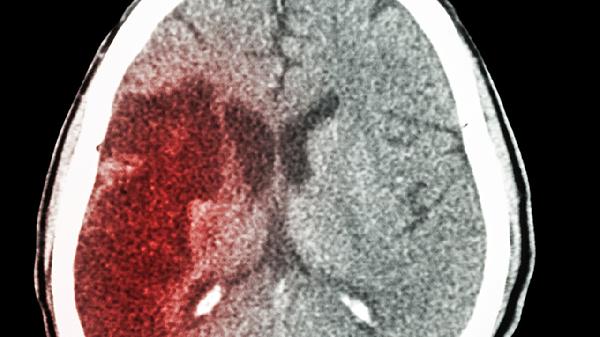

脑梗这个"隐形杀手"越来越年轻化,最近接诊的30岁患者竟有血管像60岁老人!餐桌上那些看似无害的食物,可能正在悄悄堵塞你的血管。今天就来揭开三种最危险的"血管杀手"真面目。